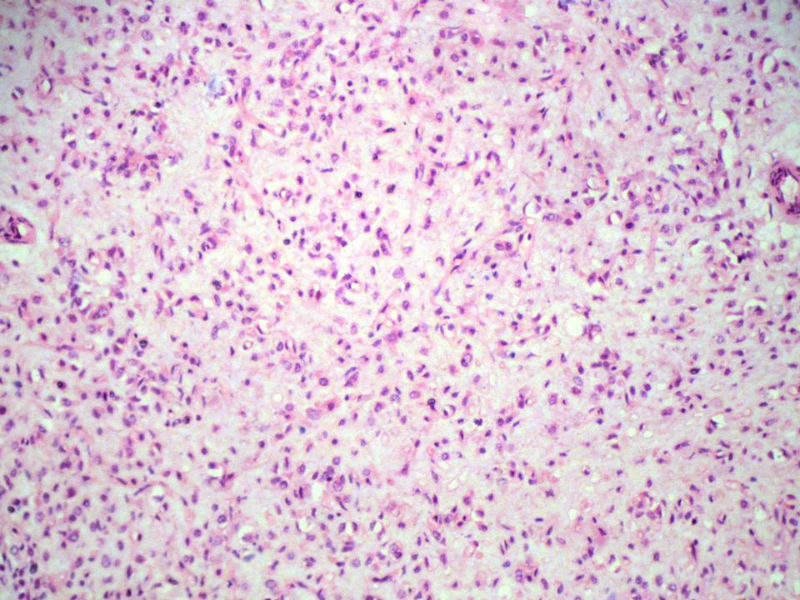

男,27岁,右股骨上段皮下肿物1年余,无明显疼痛,检查肿物明显隆起于皮下,边界清楚,手术完整切除肿物。肉眼,肿物6X6X5厘米,外观多结节状,似有包膜,切面灰白色,质韧。

特别提示:镜下核分裂3-4/HP.

1. 本例没有做KI-67,但我在前面特别提示:镜下核分裂3-4/HP.

3. 本例组织学改变与粘液性脂肪肉瘤,粘液样纤维肉瘤,纤维粘液样肉瘤,骨外粘液样软骨肉瘤都有重叠之处,且镜下并未见典型结构。由此,免疫组化结果就尤显重要。特别是专业书籍提到,突触素或嗜铬素阳性,对鉴别诊断有重要意义。我用CGA,也是在以上几个肿瘤中举棋不定而为。NSE和CK没用,其实我想用更多的抗体来证实更多的东西,但患者的经济条件不太好,遗憾!